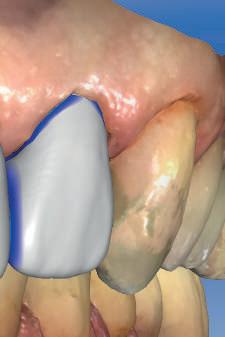

Biotipul din locaţia implantului şi poziţia implantului în relaţie cu pereţii corticali sunt factori ce pot anticipa susceptibilitatea la recesie. Un biotip de ţesut moale <2mm se asociază cu os subiacent mai subţire, defecte osoase angulare şi susceptibilitate mare la pierderea papilei după inserarea imediată a implantului. În plus, un aseme -

nea biotip este mai predispus la recesie ca reacţie la traumă şi bacterii, în comparaţie cu biotipul gros. Ca răspuns la această îngrijorare, se recomandă planificarea inserţiei implantului la cel puţin 2mm palatinal faţă de conturul vestibular al dinţilor adiacenţi; implanturile poziţionate vestibular sunt expuse riscului de recesie gingivală. În concluzie, grosimea ţesutului moale vestibular şi a osului vestibular deopotrivă reprezintă factori cheie în anticiparea apariţiei recesiei.

Rezultatul final al cazului 5 (fig. 19) prezintă recesie vestibulară de peste 2mm în jurul bonturilor cu sprijin implantar, fiind evidentă prezenţa unui ţesut moale foarte redus din cauza plasării vestibulare a implanturilor. Butler, Kinzer susţin premiza că trebuie să existe suficient volum osos vestibular, chiar şi atunci când implantul este plasat ideal, multe complicaţii fiind legate mai degrabă de poziţia implantului.

Poziţia vestibulară a implanturilor

Orientarea vestibulară a implantului va afecta peretele corticalei vestibulare

şi va induce resorbţie osoasă şi migraţia apicală a ţesutului (Saadoun & Touati). Dacă implantul nu este plasat mai palatinal şi la 3-4mm apical de marginea gingivală liberă pentru a asigura profilul de emergenţă adecvat, rezultatul estetic este compromis (Chu et al). Un studiu de 2 ani a demonstrat că implanturile poziţionate anterior au demonstrat o recesie uşor mai accentuată, decât implanturile posterioare (Bengazi et al). Plasarea vestibulară a implanturilor se poate vizualiza clar în cazul 5 (fig. 17) cu bonturile de vindecare în poziţie.